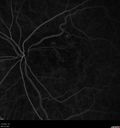

74 year old man caucasian man: The patient started having trouble with his vision after his stroke 10/9/17. He noticed after recovery that his peripheral vision had declined. He doesn't notice a difference between his two eyes. He has been having trouble focusing together his two eyes. After his stroke he was not able to read. He could trace letters but not see. He is having speech and occupational therapy at the moment. VA OD: sc20/125-2 PH20/125-2 NccJ1+ VA OS: sc20/63-2 PH20/100-2 NccJ1 Vision improved to 20/20 with Lucentis

Polypoidal Choroidal Vasculopathy Left Eye373 views74 year old man with vision loss to 20/100 over a few months. He improved to 20/20 with Lucentis. The color and ICG show the polyps.00000